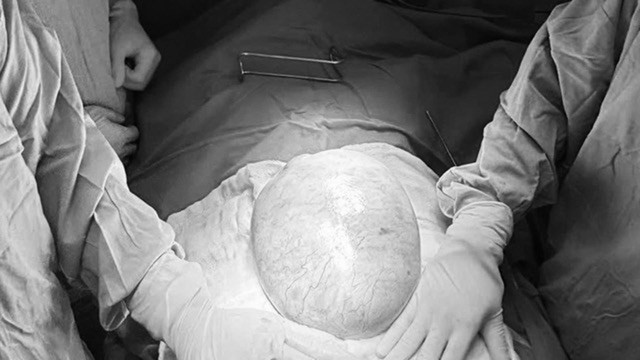

Khối u buồng trứng khổng lồ ở bệnh nhi. Ảnh BVCC.

Theo BS.CKI Nguyễn Hiền (Khoa Ngoại Tổng hợp, Bệnh viện Nhi đồng 2), khi tiến hành phẫu thuật, các bác sĩ ghi nhận khối u có kích thước khoảng 20x25x10cm, nặng gần 4kg, chiếm gần toàn bộ buồng trứng phải. Do khối u lớn, có thành phần mô đặc và nguy cơ ác tính, ê-kíp quyết định cắt trọn buồng trứng phải cùng vòi trứng phải nhằm loại bỏ hoàn toàn tổn thương. Ca phẫu thuật diễn ra thuận lợi, bệnh nhi hồi phục tốt sau mổ.